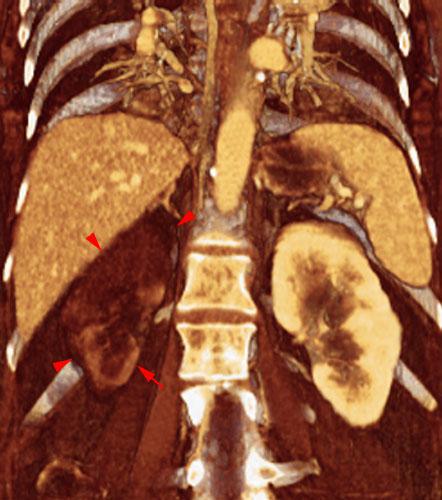

Infarto renal agudo